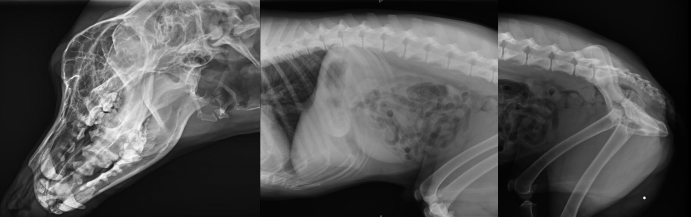

不管是人還是動物,有一項檢查是非常常見的,就是X光拍片檢查,X光檢查是傳統的影像學檢查手段,它是應用較早、普遍,價格也相對便宜。主要用于一些疾病的初步檢查,便于發現較明顯病變的組織和結構,是疾病初篩優選的檢查方式。那么,一般寵物拍X光片和人拍X光片有什么不同點,參數選擇一樣嗎?